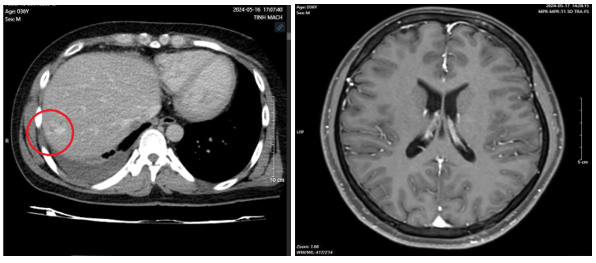

- Chụp cắt lớp vi tính ổ bụng: Hình ảnh theo dõi u máu gan phải kích thước 18x20mm

- Chụp cộng hưởng từ sọ não: Hiện tại không có bất thường

-        Chụp cắt lớp vi tính ổ bụngNốt đặc xương thân -cánh trái xương cùng kích thước 15x8mm và xương cánh chậu trái kích thước 13x9mm. Hình ảnh theo dõi u máu gan phải/ gan nhiễm mỡ

Hình 5: hình ảnh chụp cắt lớp vi tính ổ bụng sau điều trị 10 tháng không có tổn thương nghi ngờ thứ phát